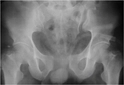

4. Tanı ve Tedavi YöntemleriPelvis bölgesi ağrısının tanısı, hastanın öyküsü, fiziksel muayene ve gerekirse görüntüleme yöntemleri (ultrason, MR vb.) ile konulmaktadır. Tedavi yöntemleri ise ağrının nedenine bağlı olarak değişkenlik göstermektedir. Genel tedavi seçenekleri şunlardır: